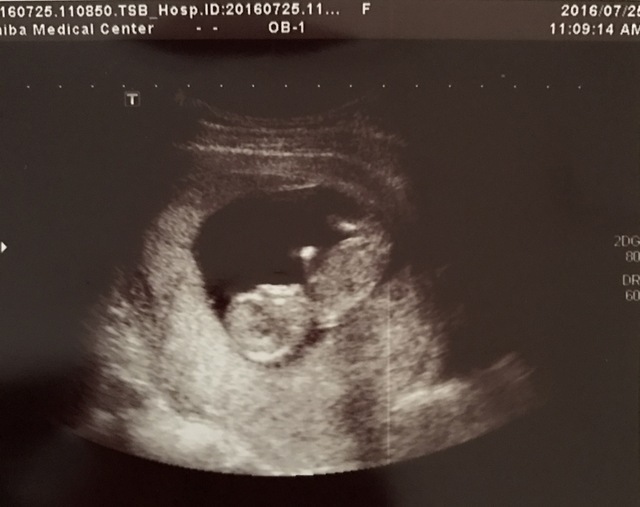

11週0日(11w0d・性別不明)|sumire0113 さん(35歳)

エコー写真撮影時のエピソード:

九州から関東への引越し後初めて新しい病院で撮ったエコー写真です。

今までのエコーから腹部エコーに初めて変わり、先生も大笑いするくらいに、ぐるんぐるんと動き回っている姿を見て感動しました。

まだつわり真っ只中だったので、これでまだ頑張れると勇気をもらいました。 そんな我が子、エコー写真を撮る瞬間にピースをしてくれた瞬間です。